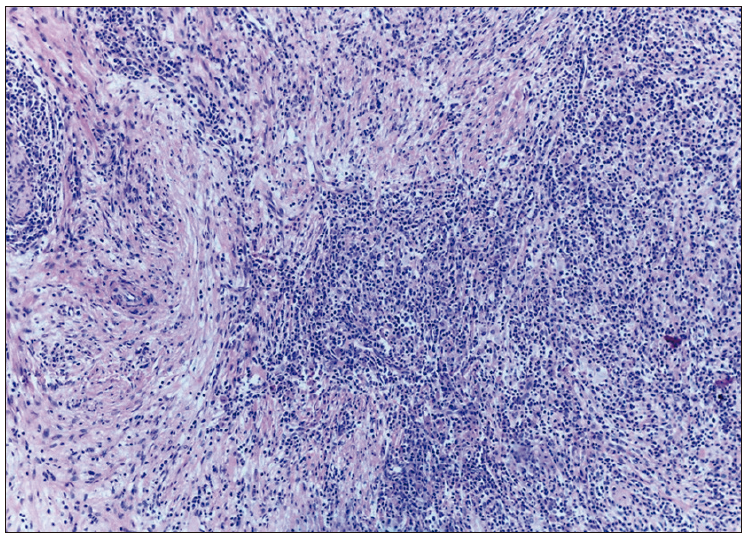

Figura 3. Se observa parénquima hepático con infiltración por numerosas células

plasmáticas, que se disponen de manera difusa y en grupos. Dichas células se acompañan de marcada fibrosis

colágena, que en algunas áreas adopta un patrón de tipo “estoriforme”

Los resultados histológicos de la pieza quirúrgica informan un infiltrado linfoplasmocitario, eosinófilos, marcada fibrosis que adopta un patrón de tipo “estoriforme” y tromboflebitis obliterativa. En la inmunohistoquímica se observa un promedio de 156 células plasmáticas IgG4 positivas. Dichos hallazgos histológicos son sugestivos de pseudotumor inflamatorio relacionado a IgG4 (Figuras 3 y 4).